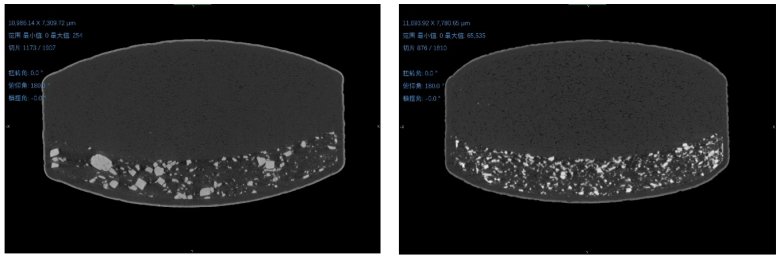

① 三維空間結構形態

左圖為原研藥,右圖為仿制藥